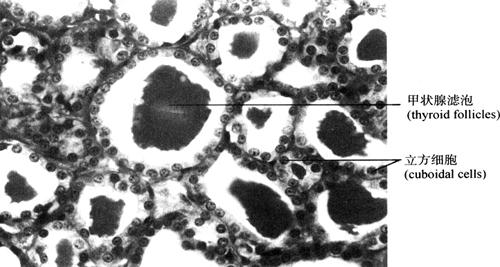

2.单层立方上皮(simple cuboidal epithelium) 由一层近似立方形细胞构成,核呈圆形,居中(图2-8)。分布于甲状腺滤泡、肾小管和卵巢表面,许多外分泌腺的腺泡细胞和小导管都为此种上皮。有吸收和分泌功能。

图2-8 单层立方上皮(400×)